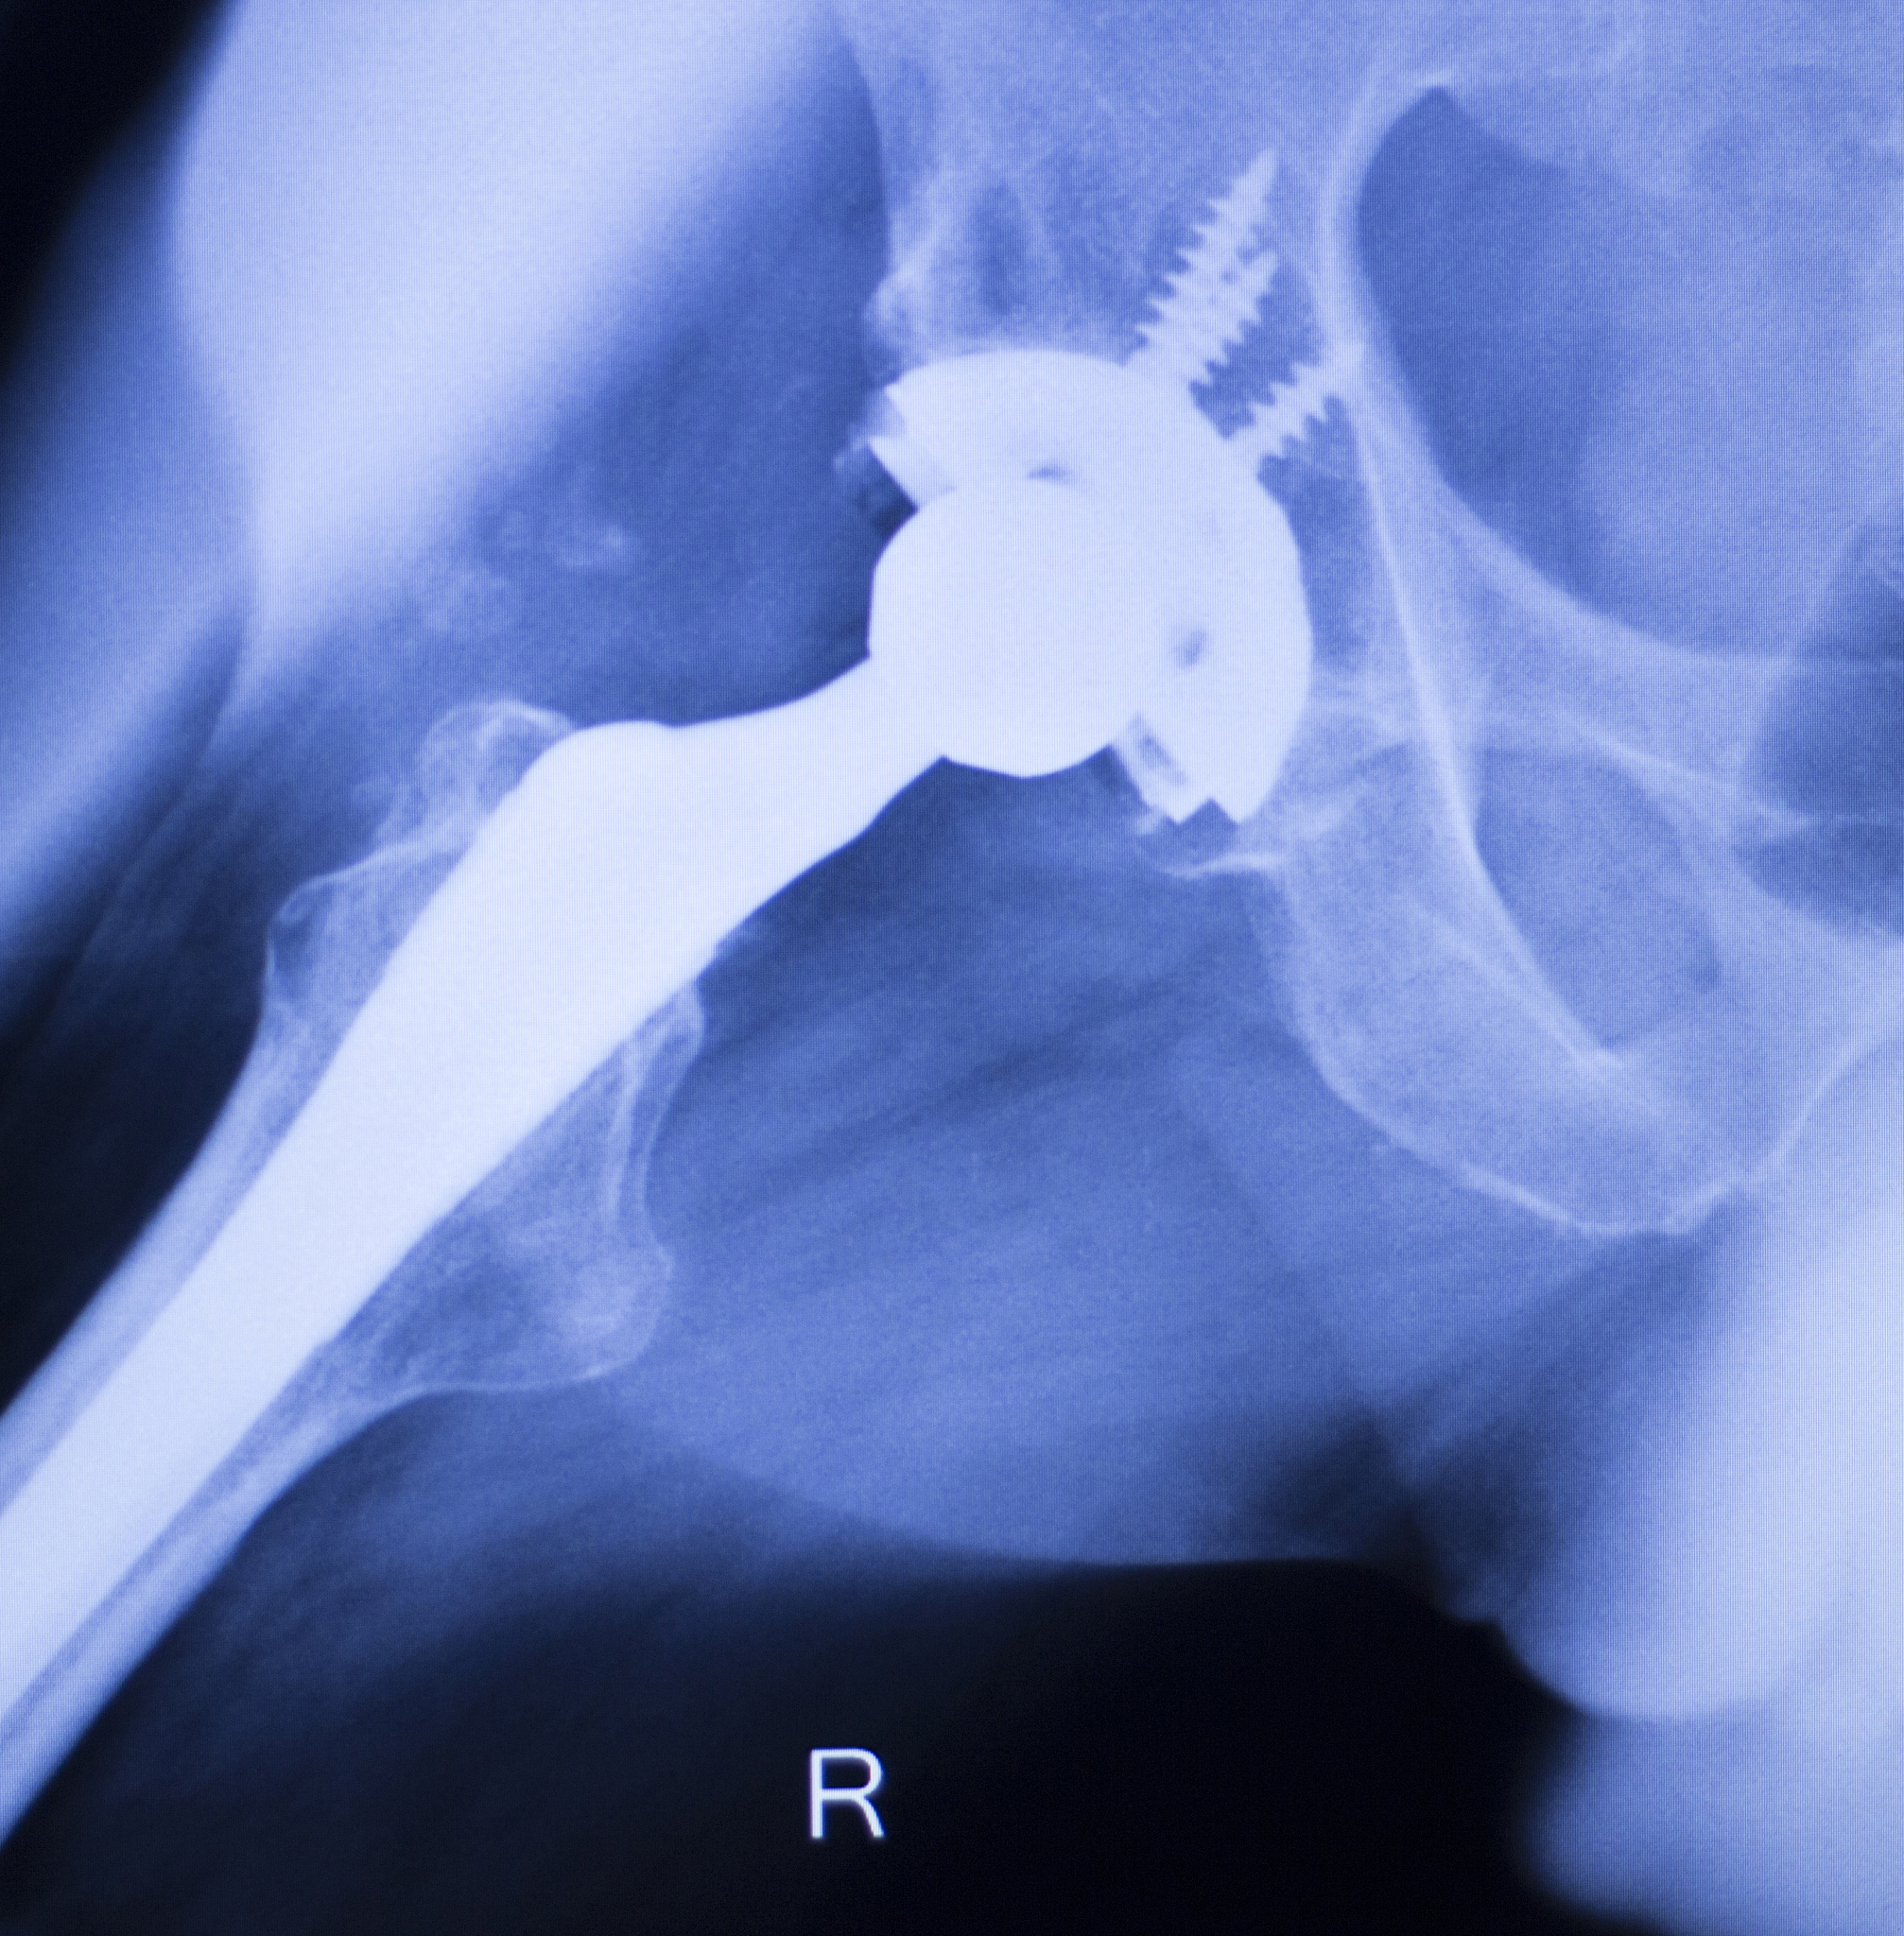

- **X光片:*可以清晰地显示骨折的部位、类型和程度。 **CT扫描:*可以提供更详细的骨折信息,有助于制定手术方案。 **MRI检查:**可以评估骨折周围的软组织损伤情况。

- 保守治疗: * 适用于骨折移位不明显、患者年龄较大或身体状况不佳的情况。 * 治疗方法包括:卧床休息、牵引固定、药物治疗(止痛、预防感染等)。* 手术治疗: * 适用于骨折移位明显、保守治疗无效或患者年轻、身体状况较好的情况。 * 手术方法包括: * **内固定术:**使用钢板、螺钉等固定骨折部位,促进骨折愈合。 * **人工关节置换术:**适用于股骨头坏死或骨折无法修复的情况,用人工关节替换受损的关节。